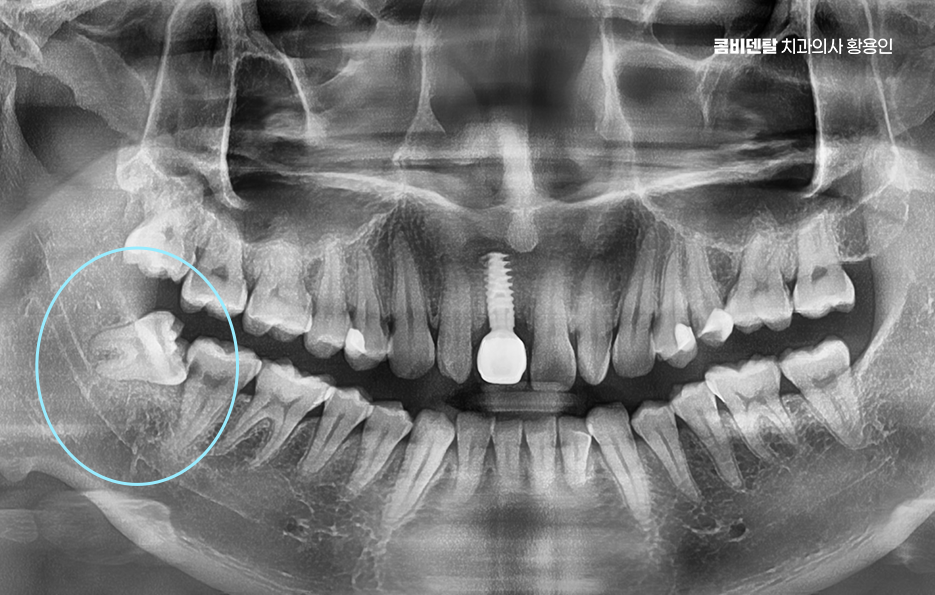

출처 아카이브 열기얼마 전부터 오른쪽 아래 어금니 근처가 묘하게 불편했어요, 처음에는 그냥 음식물이 좀 더 자주 끼는 것 같다고만 생각했는데, 어느 날부터 양치할 때 그쪽을 닦으면 묘하게 시큰한 느낌이 들었어요, 아프다고 할 정도는 아닌데 묘하게 예민하고, 시린 듯도 하고, 찜찜한 기분이 남아서 괜히 그쪽은 피해서 양치하게 되고, 그러다 보니까 오히려 더 불결하게 관리된 게 아닐까 싶은 걱정도 들기 시작했어요, 그렇게 결국 알게 된 사실은 사랑니에 충치가 생겼고, 그 사랑니 바로 앞에 있는 어금니까지 영향을 받아 충치가 함께 진행되었어요. 결국 이렇게 문제가 생기고 나니까 진작 사랑니를 뽑을 걸 하는 후회가 한꺼번에 밀려왔어요 왜 하필 그 끝에 있는 사랑니 때문에 앞에 있는 어금니까지 같이 망가졌을까, 그 어금니는 평생 써야 하는데, 이미 위치 자체가 안 좋은 사랑니 때문에 멀쩡한 어금니까지 문제가 되었다는게 안타까웠어요

이처럼 흔히 사랑니 발치에 대해 무서워서 귀찮아서 뒤로 미루게 되는 경우가 많지만 사랑니의 문제는 단순히 사랑니 뿐 아니라 주변 어금니, 잇몸에도 문제가 이어질 수 있다는 점에서 가볍게 볼 수 없는 문제라고 할 수 있는데요

다시 말해 사랑니가 문제를 일으키는 건 워낙 흔한 일이지만 사랑니 하나만 문제를 일으키는 게 아니라, 그 옆 어금니까지 같이 충치가 생기는 경우도 생각보다 많은데 특히 아래쪽 사랑니가 옆으로 누워 있는 경우에는 그 앞 어금니와 밀착돼 있어서 둘 사이가 잘 닦이지 않고 음식물이 잘 끼기 쉬운 구조라고 할 수 있었어요.

사랑니는 기본적으로 구강 내에서 가장 마지막에 나오는 치아이기 때문에 위치가 안 좋게 자라는 경우도 많고 관리가 어려운 경우도 많은데 제대로 나지 않거나, 잇몸 속에 반쯤만 머리를 내민 상태로 남아 있는 매복 사랑니는 더욱 위생관리가 어려워질 수 있었어요.

이런 사랑니는 앞 어금니와 비정상적인 접촉을 하게 되면서 음식물이 계속 끼고 세균이 쌓이게 되며 아무리 양치질을 잘한다고 해도 물리적으로 칫솔이 닿기 어려운 구조라서 결국 충치나 염증으로 이어지는 경우가 많은 거예요

문제는 여기서 끝나지 않고 누운 사랑니와 앞 어금니 사이에 충치가 동시에 생기는 경우는 치료가 더 복잡해질 수 밖에 없는데 왜냐면 사랑니가 옆으로 누워 있으니까 앞 어금니 뒷면에 생긴 충치를 제대로 보기도 어렵고, 치료 기구가 들어갈 공간도 부족해져서 충치 치료가 더 까다로워지는 것이며 특히 앞 어금니 뒷면에 생긴 충치는 환자도 자각하기 어렵고, 진단 시기도 늦어지는 경우가 많아서 이미 신경까지 손상됐거나 신경치료가 필요한 상태로 발견되는 일도 많이 있었어요